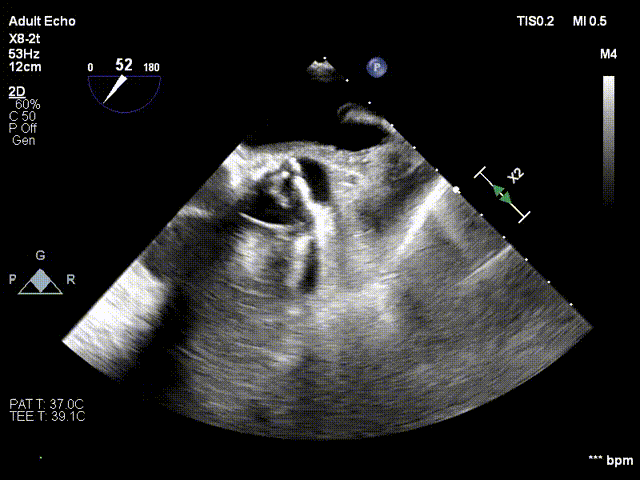

术前、术后超声对比

术前

术后超声显示瓣口未见明显反流,无瓣周漏,主动脉瓣前向血流加速Vmax=1.65m/s,有效开口面积1.61cm²,PGmean=4mmHg。术后监测,心率心电正常,无传导阻滞。患者生命体征稳定。本次手术植入瓣膜定位准确,操作简便,症状即刻改善,手术圆满成功。